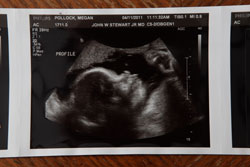

What a day we had on April 11! We started the day at Dr. Stewart’s office. Of course, it started with a pretty significant delay due to all of the women having babies. We met a new ultrasound tech, so we were curious to see what she thought as she took her first glimpse at our lil Peanut.

We find it funny that each time someone new checks in, they mention how long Peanut’s legs are. Our little one is measuring right on target, maybe even a few days ahead. Peanut weighs 3lbs 6 oz with A LOT of hair.

We had a feeling it would be one extreme to another. I did not have hair until after 1, and Randy was blessed with a fro. Our priceless moment arrived when we saw Peanut’s mouth moving. On the other end, Dr. Stewart mentioned the ventricles have slightly increased, meaning there is more water on the brain. Other than that everything checked out pretty good.